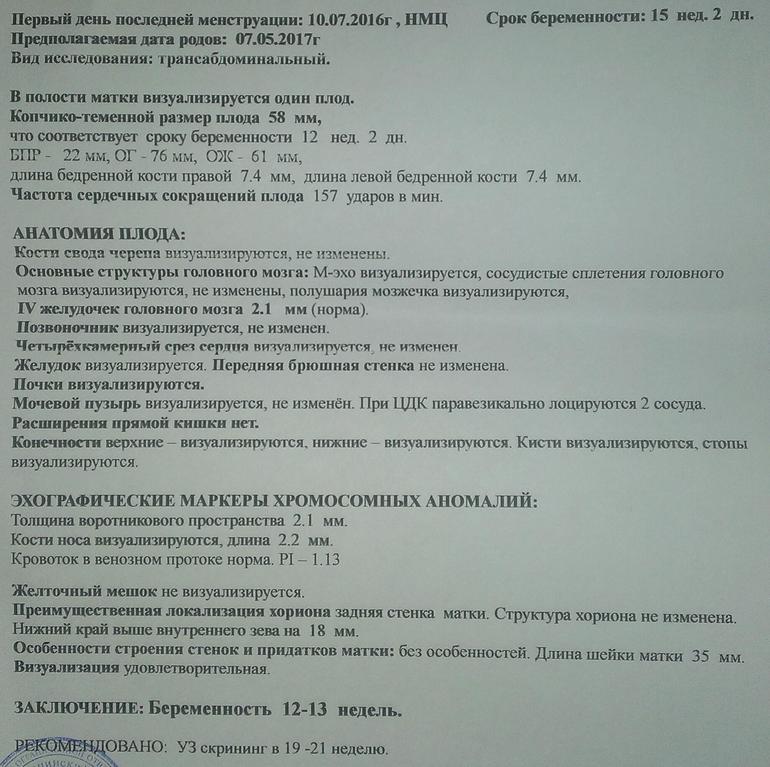

Первый скрининг УЗИ на 13 неделе: Что нужно знать